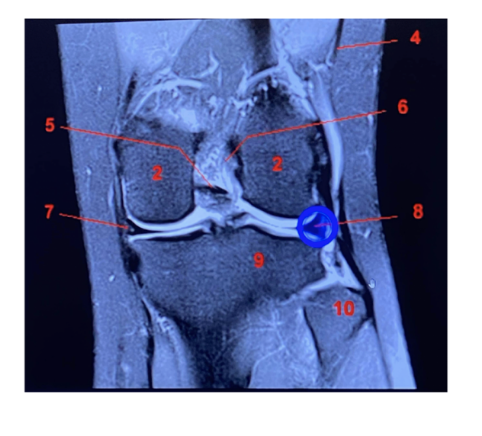

label each

2- lateral and medial condyles of femur

4- vastus lateralis muscle

5-posterior cruciate ligament

6- anterior cruciate ligament

7- medial meniscus of knee

8- lateral meniscus of knee

9-tibia

10-fibula